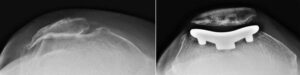

Patellofemoral replacement implants. The metal femoral implant (left) resurfaces the trochlear groove of the femur. The round plastic patellar implant (right) attaches to the underside of the kneecap.

(Left) This X-ray is taken from above the knee. The patella and the trochlear groove of the femur have become deformed due to osteoarthritis. There is now bone rubbing on bone. (Right) The same knee after patellofemoral replacement. The patellar implant on the underside of the kneecap does not show in an X-ray.

Front view of a knee after patellofemoral replacement.